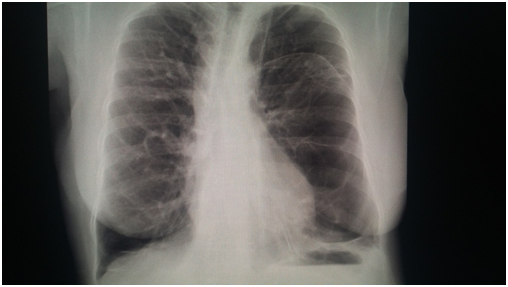

Female of 59 years old, exposed to biomass smoke (index=100 hrs/year), followed as Chronic Obstructive Lung Disease during 9 years; her main symptom has been dyspnea, vital signs HR 86 per min, RR 20 per min, 110/78 mmHg, body temperature 36.6°C, very severe obstruction in spirometry, low Diffusion Capacity, increased Residual Volume, Pulmonary Arterial hypertension by echocardiography (47 mmHg) and arterial gases pH 7.38, PaCO2= 47 mmHg, PaO2 66 mmHg, HCO3 =21.6 and O2 saturation 92.5% with oxygen supply. Radiographic studies Figure 1 showed, bullous emphysema at left lung in conventional chest radiography; and, neurofibromatosis lesions in both hands (Figure 2) and feet (Figure 3) and Computed tomography revealing bilateral emphysema and bullae (Figure 4).

Figure 4 Bullous emphysema 2.